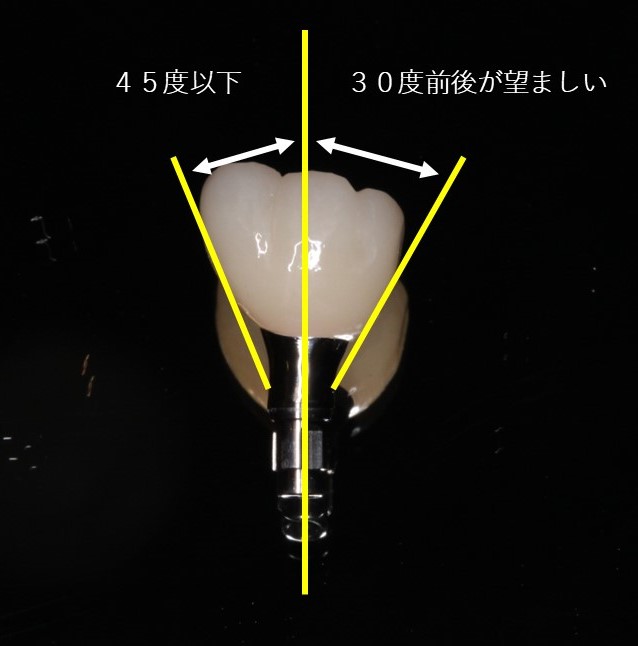

歯は、歯冠方向の1方向にしか抜けてこないため、歯冠部分を削り分割します。